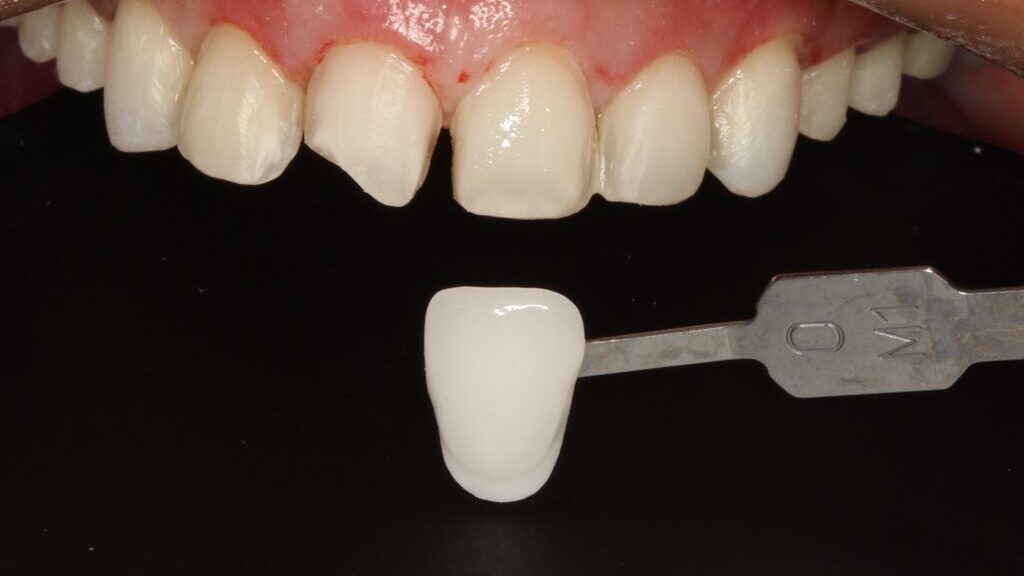

Case Study: The Missing Central Incisor – A Simple Method of Recording Emergence Profile

The loss of a tooth can be a stressful event for any individual. Upon learning that a tooth in the esthetic zone has been lost, or is going to be extracted, a patient’s immediate statement is almost always: “I don’t want to lose a tooth!” followed by the question: If that’s going to happen, how do … Read more